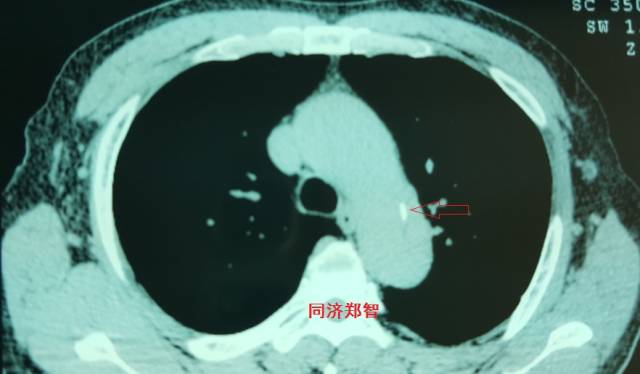

病例五

平扫CT提示主动脉弓层面及右肺动脉层面均可见主动脉血管腔内的内膜片影(红色箭头所示),CTA显示为A型主动脉夹层。